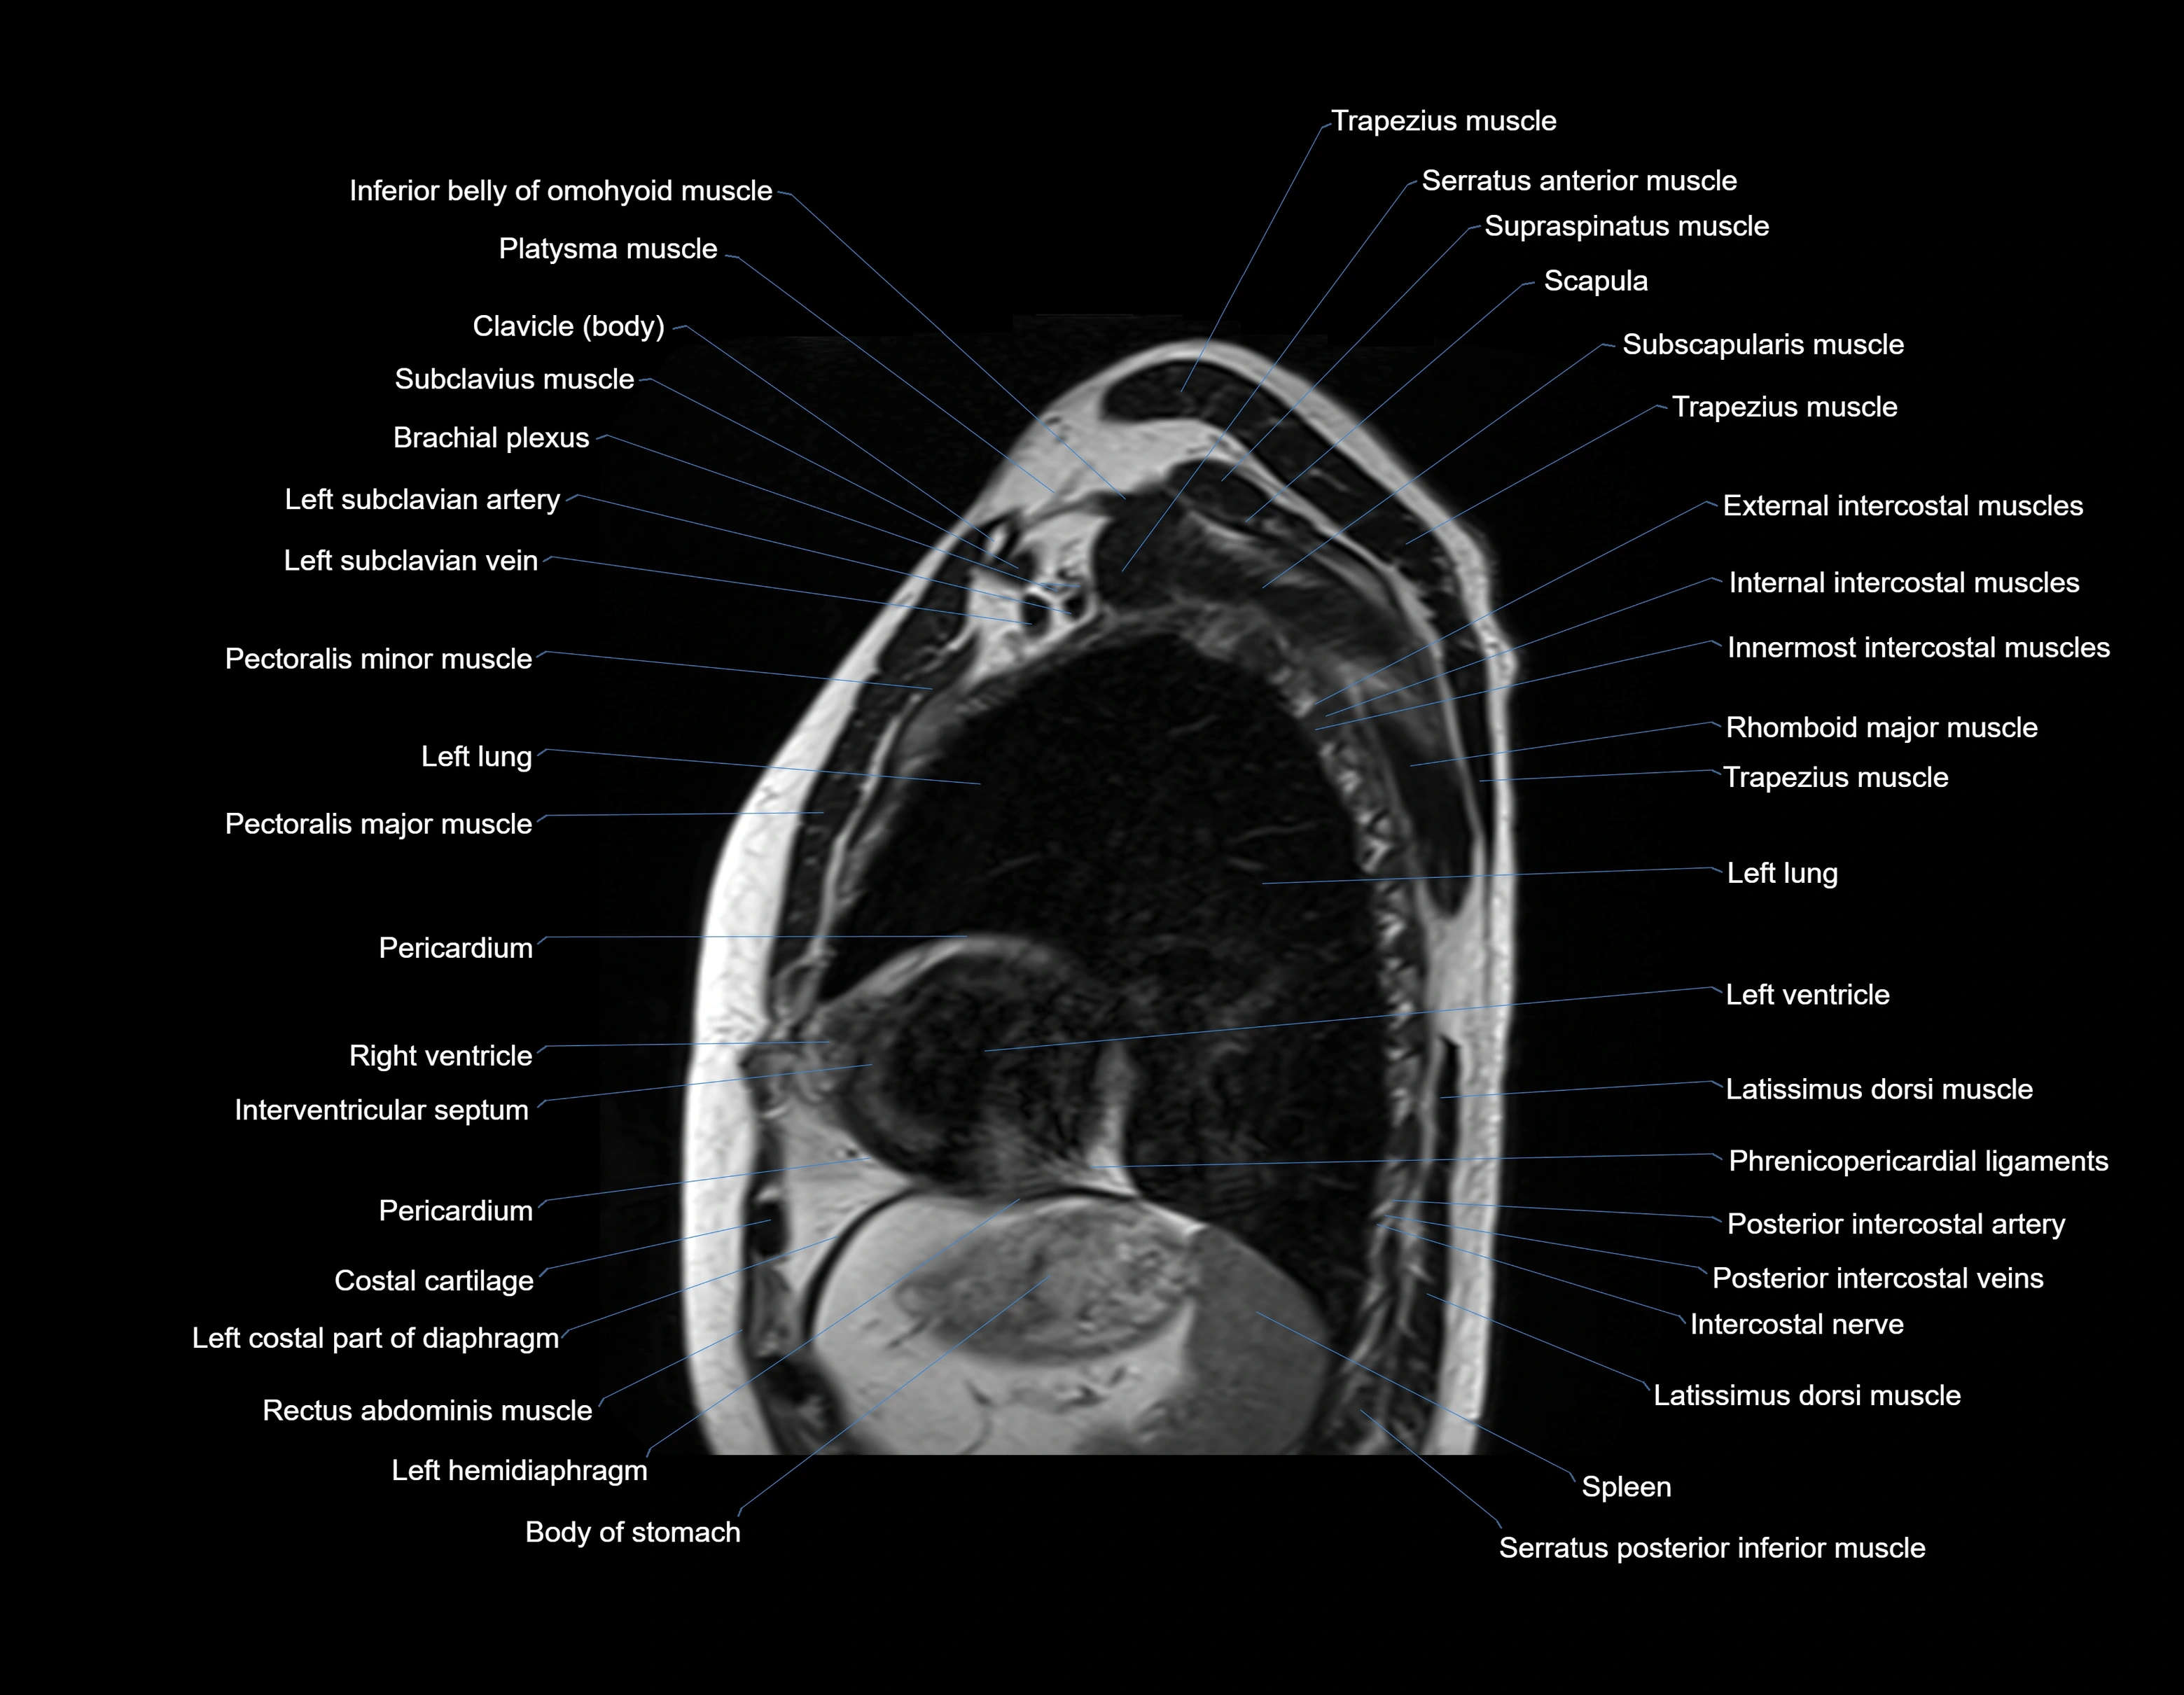

MRI images